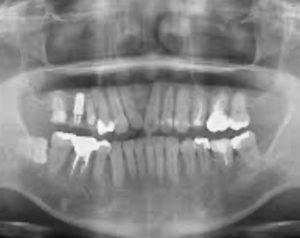

※歯科医師会提供

・向かって右側が患者さまの左側の歯です。

・硬い組織である歯と骨は白く写っています。

・柔らかい組織である歯茎や血管、神経は黒く写ります。

・虫歯も黒く写ります。

・均一な真っ白に写っているところは、治療跡の人工物です。

歯科医師はこのレントゲン画像から、非常に多くの情報を得て診断を行います。

例えば…

① つめもの・かぶせものの下にできている虫歯の進行度。

②歯を支えている骨の溶け具合。

③歯の根の先の炎症状態の有無とその重症度。

④歯ぐきの下に隠れている歯石があるか、またその付着状態。

⑤親知らずがあるか。それが他の歯に影響を与えていないか。

⑥顎の関節の形態に問題は無いか。

⑦歯の神経は残っているか。

他にもレントゲンには多くの情報が表れており、患者様の口腔内の状態を適切に診断するために必要不可欠なツールです。